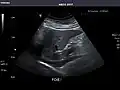

Renal ultrasonography

Ultrasound scan of a kidney (right side)

Ultrasonography of the kidneys is essential in the diagnosis and management of kidney-related diseases. The kidneys are easily examined, and most pathological changes in the kidneys are distinguishable with ultrasound.[7]

Kidneys: Right and left kidneys measure 11.5 cm and 12 cm in length respectively. No hydronephrosis. Small left lower pole kidney cyst.